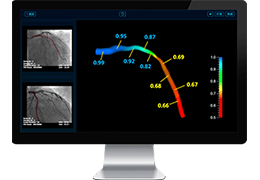

ANYTHINK 经导管主动脉瓣膜置换术分析系统